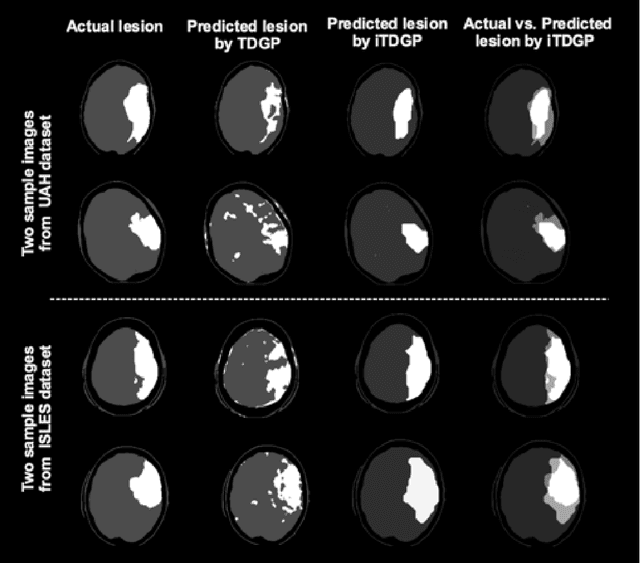

Abstract:As one of the leading causes of mortality and disability worldwide, Acute Ischemic Stroke (AIS) occurs when the blood supply to the brain is suddenly interrupted because of a blocked artery. Within seconds of AIS onset, the brain cells surrounding the blocked artery die, which leads to the progression of the lesion. The automated and precise prediction of the existing lesion plays a vital role in the AIS treatment planning and prevention of further injuries. The current standard AIS assessment method, which thresholds the 3D measurement maps extracted from Computed Tomography Perfusion (CTP) images, is not accurate enough. Due to this fact, in this article, we propose the imbalanced Temporal Deep Gaussian Process (iTDGP), a probabilistic model that can improve AIS lesions prediction by using baseline CTP time series. Our proposed model can effectively extract temporal information from the CTP time series and map it to the class labels of the brain's voxels. In addition, by using batch training and voxel-level analysis iTDGP can learn from a few patients and it is robust against imbalanced classes. Moreover, our model incorporates a post-processor capable of improving prediction accuracy using spatial information. Our comprehensive experiments, on the ISLES 2018 and the University of Alberta Hospital (UAH) datasets, show that iTDGP performs better than state-of-the-art AIS lesion predictors, obtaining the (cross-validation) Dice score of 71.42% and 65.37% with a significant p<0.05, respectively.